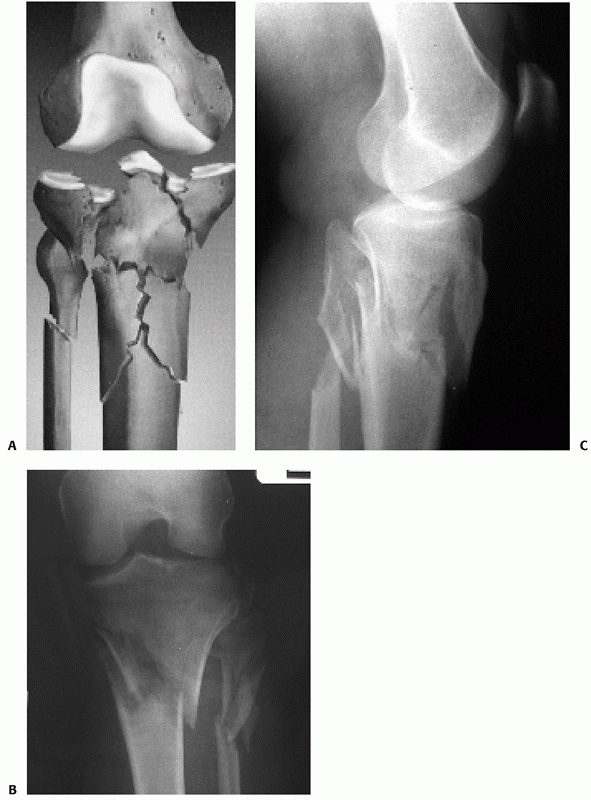

tibial plateau fractures. They provide excellent detail of the fracture

pathoanatomy and serve as a critically important aid to preoperative

planning for operative approaches and fixation techniques. Although CT

may be used to help decide on the need for surgery, there are no good

data to indicate that the additional detail apparent on CT helps

determine which fractures will benefit from surgery. CT typically

demonstrates more articular displacement and comminution than is

apparent on plain films.102 CT has

been shown to help surgical planning and to lead to more reliability in

classifying the fracture and deciding on a treatment plan.32,176

The location of depressed fragments, the size of articular segments,

and the location and orientation of fracture lines are important

details in planning an operative strategy, and they are best visualized

on CT. Three-dimensional reconstructions have been increasingly used

and found to demonstrate spatial relationships of fracture fragments

better than plain radiographs.18 In one study, the addition of spiral CT with three-dimensional reconstructions frequently resulted in

modifications and adjustments in operative plans compared with using plain radiographs alone102,176 (Fig. 53-6).

![]() |

FIGURE 53-6 A.

AP radiograph shows a high-energy bicondylar tibial plateau fracture but further characteristics of the injury are difficult to define. An axial CT (B) and coronal reconstruction (C) show the degree of comminution and identify major fragments but do not provide detail about the overall size and alignment of the fragments. (continues) |

fractured plateau that may be visualized in any two-dimensional plane

or with high-quality three-dimensional images.52

Three-dimensional images from multidetector CT scans provide detail of

the fractured proximal tibia, which enables the surgeon to assess

comminution, depression, and fracture location more accurately than

previously possible.100,106

FIGURE 53-6 (continued) (D,E)

High-quality three-dimensional reconstructions provide additional assessment of the fracture morphology for preoperative planning. |